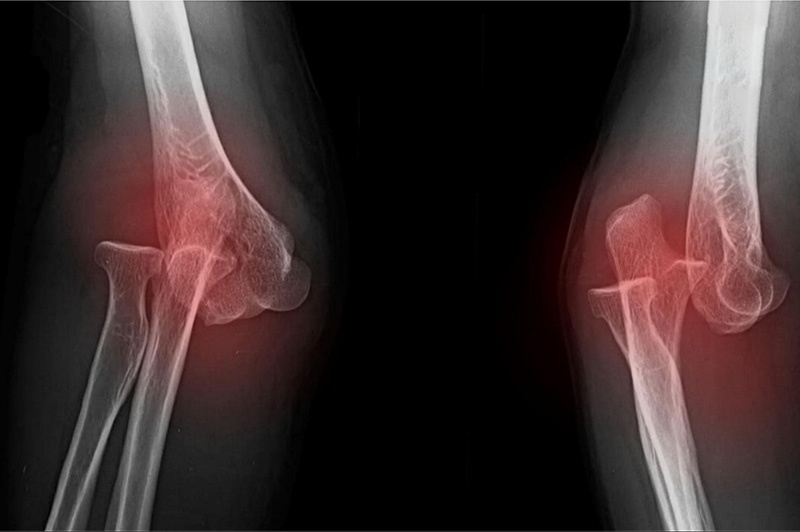

Việc chẩn đoán trật khớp khuỷu tay có thể gồm 2 bước là thăm khám lâm sàng và chẩn đoán hình ảnh để bác sĩ xác định mức độ chấn thương và đưa ra biện pháp điều trị phù hợp.

2. Chẩn đoán hình ảnh

Sau khi tiến hành thăm khám lâm sàng, một số phương pháp chẩn đoán bằng hình ảnh có thể được thực hiện để xác định rõ hơn cấu trúc của khớp:

• Chụp X-quang: Đây là phương pháp hiệu quả nhất để xác định tình trạng trật khớp và những chấn thương khác. Chụp X-quang có thể giúp chỉ ra hướng của trật khớp.

• Chụp cắt lớp vi tính CT: Nếu các chi tiết của xương khó xác định trên hình ảnh X-quang, bác sĩ có thể yêu cầu thực hiện chụp CT.

• Chụp cộng hưởng từ MRI: Phương pháp giúp đánh giá tổn thương ở dây chằng nhưng thường ít khi được yêu cầu thực hiện tại thời điểm trật khớp.

Phương pháp chụp CT và MRI thường được thực hiện sau khi khuỷu tay bị trật đã được đặt trở về đúng vị trí.